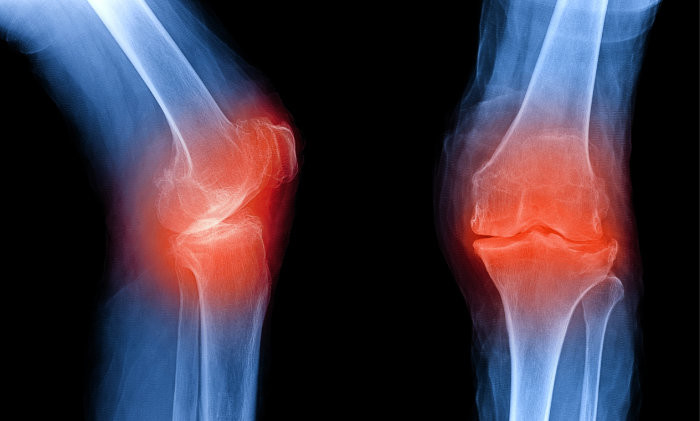

사람들이 나이가 들어감에 따라 자연적으로 관절이 안 좋아지는데요. 우리나라 성인의 만성질환 1위가 관절염이라고 하니 관절염으로 인한 통증으로 많이 불편해 하는 현실입니다. 관절염 통증은 많은 이유가 있겠지만 관절 사이에서 완충 작용을 하는 연골이 닳아서 충돌하면서 발생하는 경우가 많습니다. 이 연골의 주 성분이 콘드로이친 이라는 성분인데요.이 성분이 떨어지면 각종 관절염, 근육통 등 증상이 발생하게 됩니다. 콘드로이친은 우리 몸에서 스스로 생성되지 않는 성분으로 꼭 섭취를 통해서만 보충이 가능하다고 하네요.

콘드로이친의 가장 큰 효능은 바로 연골 감소 예방입니다. 콘드로이친은 연골에 영양분을 공급하는 역할을 합니다. 연골에 충분한 영양분들 공급하여 연골의 탄력과 힘을 보충하여 연골이 마모되는 것을 예방해 줍니다. 한 실험울 통해서 콘드로이친을 일정하게 섭취한 사람과 아닌 사람의 연골 마모 속도가 2배 이상 차이가 난다는 결과가 있습니다.

콘드로이친 효능 2. 통증과 염증 감소

관절 속 충격완화 및 충격을 방지하는 역할을 하는 콘드로이친 성분으로 하여금 연골 형태 및 탄력을 유지시킴으로 통증은 완화시키고 염증은 억제하는데 도움이 됩니다. 연구 결과 통증 완화 감소 정도가 소염진통제 만큼 뛰어난 것으로 알려져 있습니다.

콘드로이친 효능 6.연골의 재생

콘드로이친은 연골 손상을 막을 뿐만 아니라 손상된 연골 주성분인 연골세포를 재생시킴으로써 연골 기능을 향상시키는데 도움을 주어 연골의 통증으로 고통 받는 분들에게는 보행 편의성을 증대시켜 삶의 질을 향상 시킬 수 있습니다.